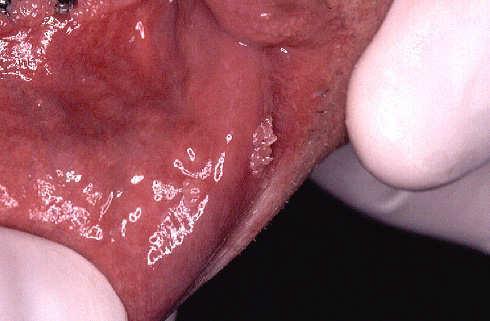

Presence of papilloma also of this of the low lip.

Simultaneous treatment with the laser of the two papillomas of the low lip, also here without Anestesie.